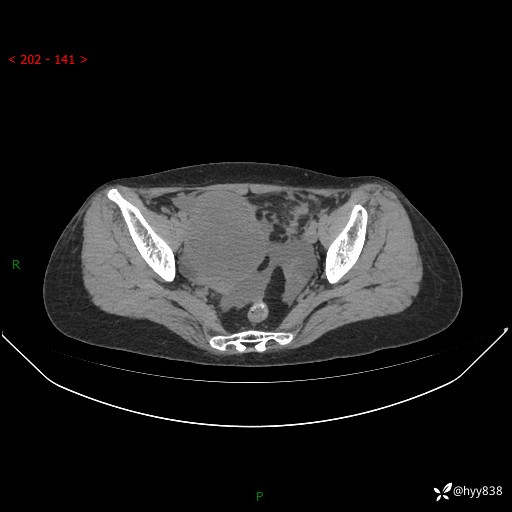

腹盆CT平扫

增强